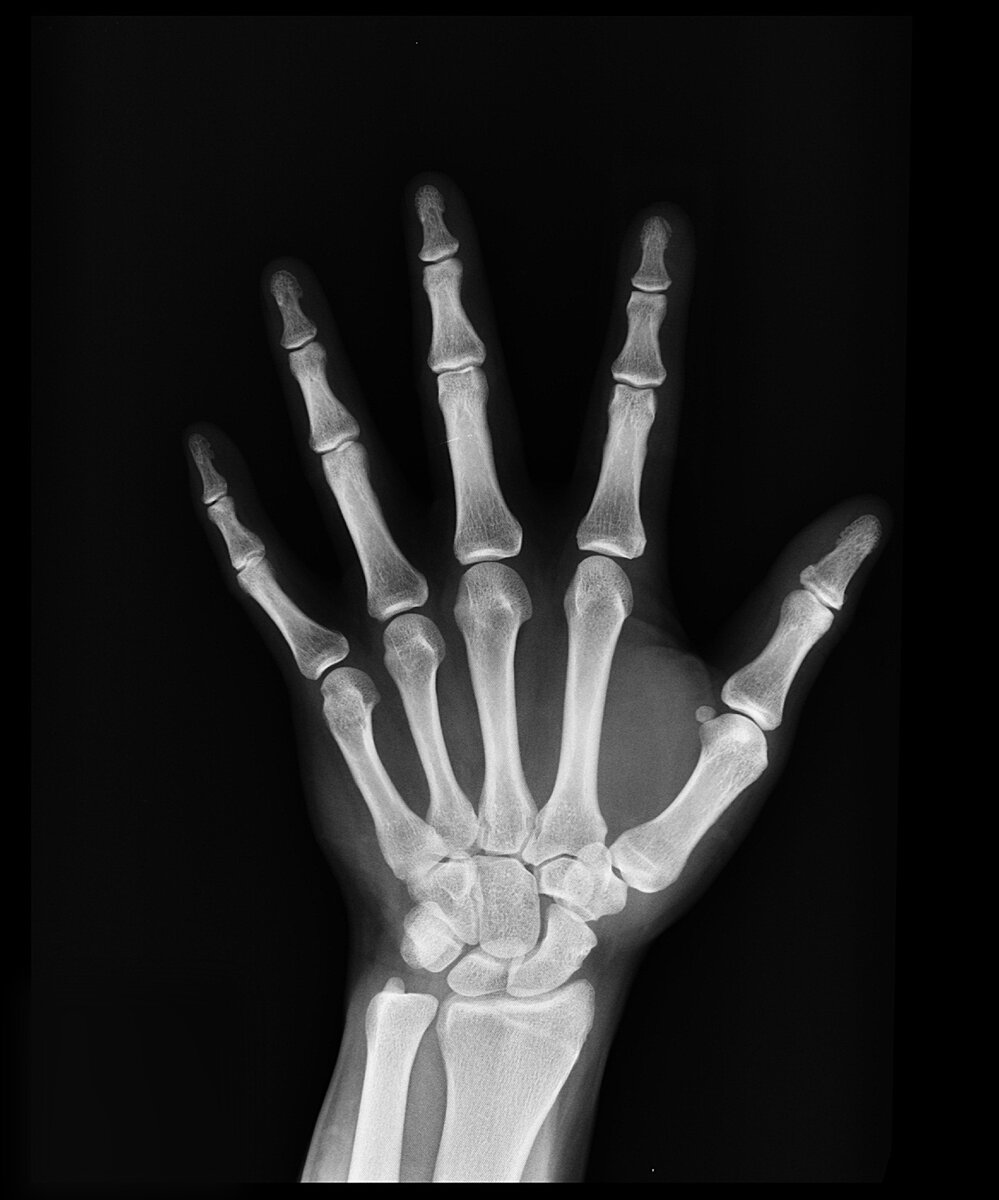

Открытие рентгеновского излучения

Эксперименты Рентгена показали, что икс-лучи возникают в месте столкновения катодных лучей с преградой внутри катодной трубки. Учёный сделал трубку специальной конструкции – антикатод был плоским, что обеспечивало интенсивный поток икс-лучей. Благодаря этой трубке (она впоследствии будет названа рентгеновской) он изучил и описал основные свойства ранее неизвестного излучения, которое получило название – рентгеновское.